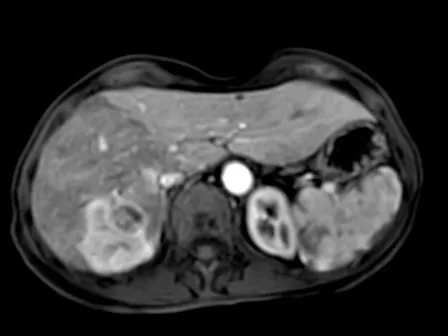

Over the span of three intensive half-days, participants will review and discuss a large selection of CT and MRI liver cases under the guidance of Prof. Giuseppe Brancatelli. Each session starts with short lectures, followed by the live presentation of selected cases, during which participants will be actively involved in describing findings, proposing differential diagnoses, and reaching a final conclusion.

After each case discussion, a concise 1–2-slide summary will highlight key diagnostic points, underlying pathology, and relevant imaging criteria.